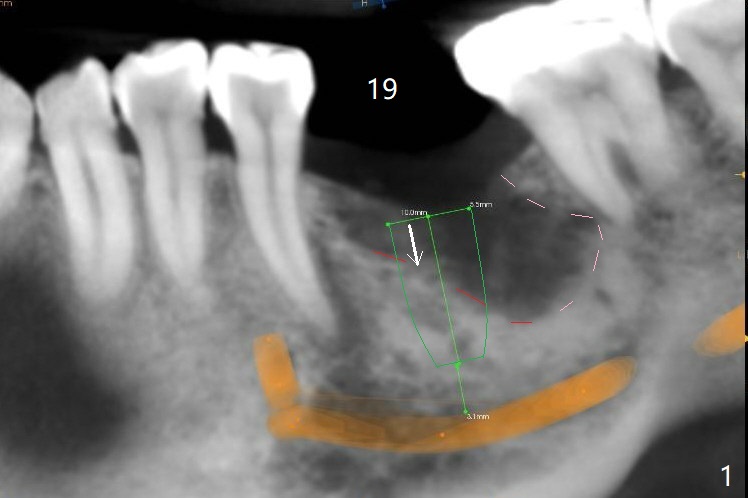

CT taken 4-5 months post extraction shows the outline of the socket at #19 (Fig.1 pink and red dashed line). By the time of surgery (6-7 months post extraction), the ridge looks narrow (Fig.2). In fact the socket does not heal (Fig.3). Osteotomy starts at the mesial border of the socket (Fig.4). When a 5x10 mm dummy implant is placed, the axis begins to be tilted distally (Fig.5 red line), which is more obvious when a definitive longer implant (5x11.5 mm) is placed (Fig.6,7). Osteotomy (Fig.1 arrow) at the mesial slope of the socket (red dashed line) should be initiated more mesial to compensate for the distal drifting while osteotomy is being increased and the implant is being placed. The distal defect is filled with Vanilla graft. Probably due to the mesial slope and the distal defect, the primary stability is <10 Ncm. A healing screw is placed with Vanilla allograft/autogenous bone. The bone forms coronal to the implant 4 months postop (Fig.8 *), which is removed for uncover. The mesial gingival embrasure of the permanent crown is large (Fig.9 *), as related to the mesial undercut associated with a 5.7x4 mm A 15 degree angled abutment (Fig.10). Reduction in the undercut should be able to help lab decrease the gingival embrasure (Fig.11 red line). The bone density around the implant increases with distinct trabecular pattern consistent with stress 5 months post cementation (1 year postop, Fig.12).